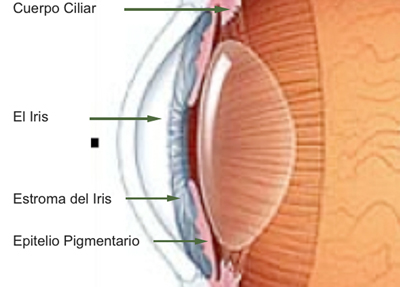

Separa la cámara Anterior de la cámara Posterior en el Ojo, y esta situado por delante del Cristalino; se compone de 3 capas: la hoja Anterior del Iris (membrana pupilar) cuya atrofia parcial genera las criptas de Fuch´s, el Estroma, capa fibrovascular y pigmentada, no tiene epitelio y su origen es mesodérmico; la Posterior debajo del estroma, es una capa de células epiteliales pigmentadas con un grosor de 2 células, conocida como el Epitelio pigmentario del Iris cuyo origen viene del neuroectodermo.

El Iris se divide 2 regiones principales:

1- La Zona Pupilar es la región mas interna que conforma el borde de la pupila ;(desde el borde periférico del collarete)

2- La Zona Ciliar es el resto del iris y se extiende hasta su origen en el cuerpo ciliar

El Collarete que separa la zona pupilar de la ciliar y es la porción mas gruesa del iris, es un vestigio de la cubierta de la pupila embrionaria. La Raiz de iris es la porción mas periférica y la mas delgada, esta unida a la esclera y a la porción anterior del Cuerpo Ciliar. El Iris y el Cuerpo Ciliar componen la Úvea Anterior.

La vascularización proviene de las arterias ciliares largas y las ciliares anteriores, que penetran formando una malla radial en el estroma iridiano.

Existe el círculo vascular mayor del Iris situado en la periferia que ya es estroma del cuerpo ciliar, y el círculo menor en el collarete.